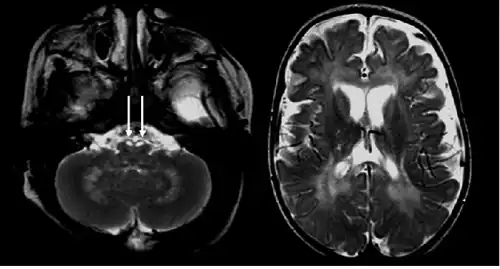

Symptoms in asymptomatic infantile-onset (<12 months after birth) and later-onset Krabbe disease present themselves differently. Of individuals with infantile-onset Krabbe disease, 85–90% display progressive neurologic deterioration in infancy and death before the age of two.[7] Symptoms include irritability, fevers, limb stiffness, seizures, feeding difficulties (like GERD), vomiting, staring episodes, and slowing of mental and motor development. In the first stages of the disease, doctors often mistake the symptoms for those of cerebral palsy. Other symptoms include muscle weakness, spasticity, deafness, optic atrophy, optic nerve enlargement,[8] blindness, paralysis, and difficulty when swallowing. Prolonged weight loss may also occur.

Marked enlargement of the prechiasmatic segment of the optic nerves